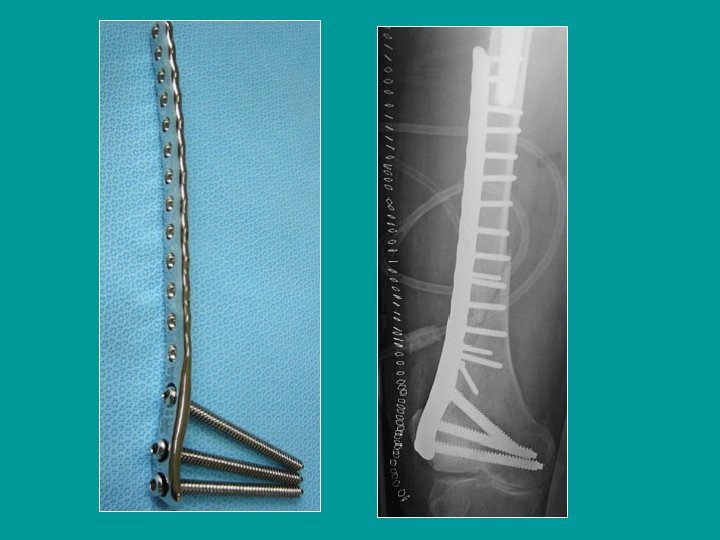

Ostéosynthèse des fractures distales du fémur Lame-plaque AO Plaque vissées

Ostéosynthèse des fractures distales du fémur Vis-plaque de Judet

Fractures comminutives Lame-plaque AO Plaques en pont sur la comminution

Mise en place d’une vis-plaque de Judet

Plaque vissée classique

Mise en place d’une plaque de Chiron